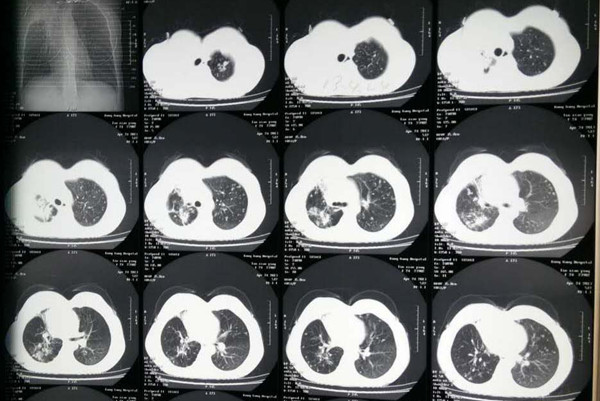

关于肺结核复发某些机构给出的定义是患者符合肺结核诊断标准,达到“治愈”标准或“完成治疗”标准,在随访观察过程中,至少1次痰抗酸杆菌涂片或痰结核分枝杆菌培养结果为阳性,可同时出现活动性肺结核的临床表现或肺部x线病灶征象。那么治愈的肺结核为什么会复发呢,肺结核复发怎么治呢?下面我们就一起来看下。